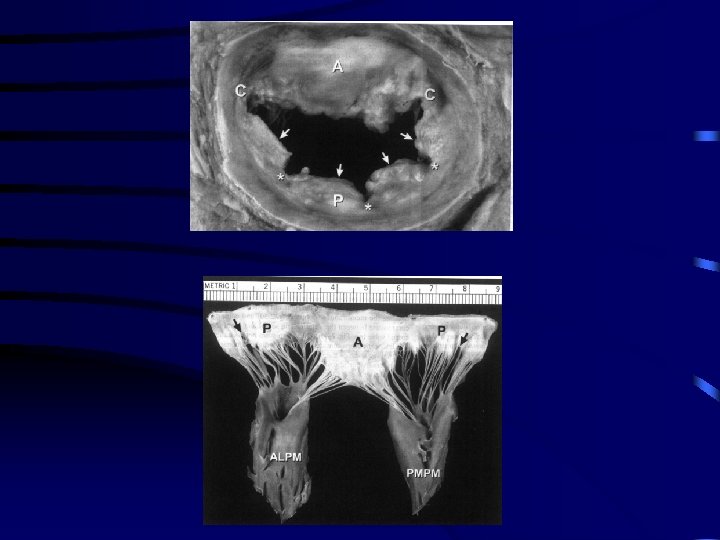

Repaso anatómico • Anillo mitral: Condensación fibrosa: zona de inserción de valvas a VI • Valva anterior: – Unido a continuidad fibrosa aorto mitral – Relativamente no distensible en mayoría – Doble irrigacion • Valva posterior: – 2/3 posteriores anillo fibroso – Se une directamente a VI o a memb subvalvular

Repaso anatómico • El anillo fibroso: en continuación con cuerpo central fibroso del corazón (unión anillo mitral, valvas mitrales, raíz aórta y septum membranoso) • El velo anterior: mayor movilidad que el posterior

Repaso anatómico VELO ANTERIOR: – Cuadrangular. – Se inserta en 1/3 anillo valvular – Tiene continuidad fibrosa con válvula aórtica VELO POSTERIOR: – Más grande – Se inserta en 2/3 de circunferencia anular – En toda su extensión se une a pared diafragmática ventrículo